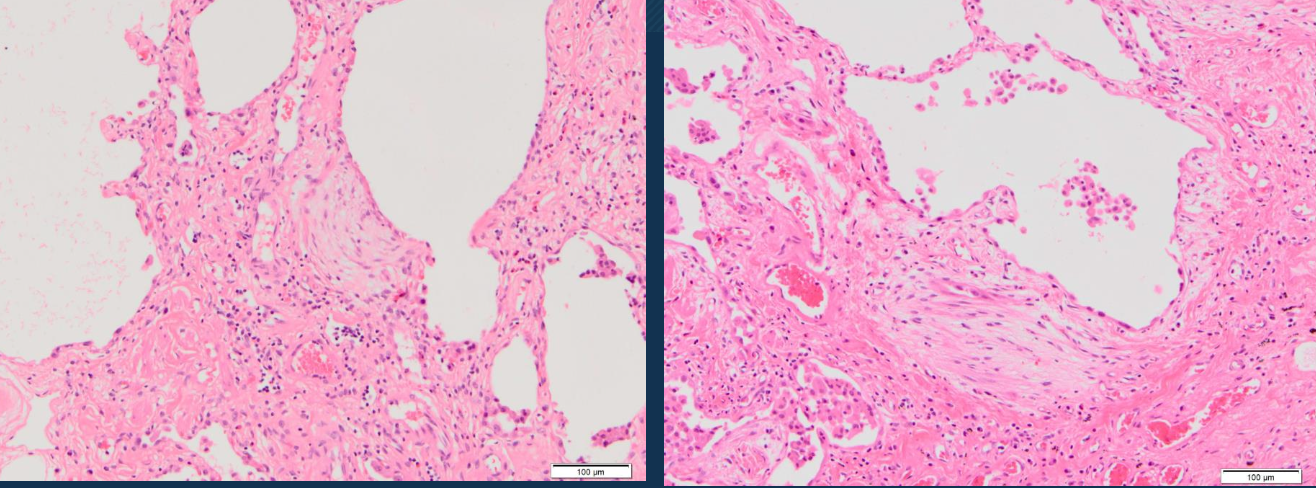

Neumonía intersticial inespecífica tipo:

Celular

¿Cómo se encuentran distribuidas las células en la neumonía intersticial inespecífica?

Linfocitos y células plasmáticas con distribución uniforme o en parche

fibrosante

Neumonía intersticial inespecífica tipo fibrosante, microscópicamente

Lesiones intersticiales difusas o en parches en la misma etapa de desarrollo (esto lo diferencia de la neumonía intersticial usual (UIP) en la fibrosis pulmonar idiopatica, donde las lesiones son de diferentes edades/etapas)

Lo que no se ve en NSIP (a diferencia de otras enfermedades intersticiales)

No hay focos fibroblásticos.

No hay patrón en panal de abeja (honeycombing).

No hay membranas hialinas.

No hay granulomas.